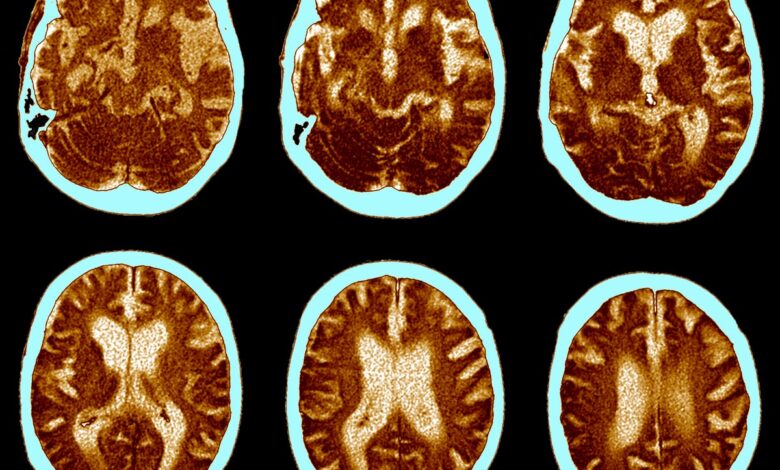

CT mozku Alzheimerovy choroby.